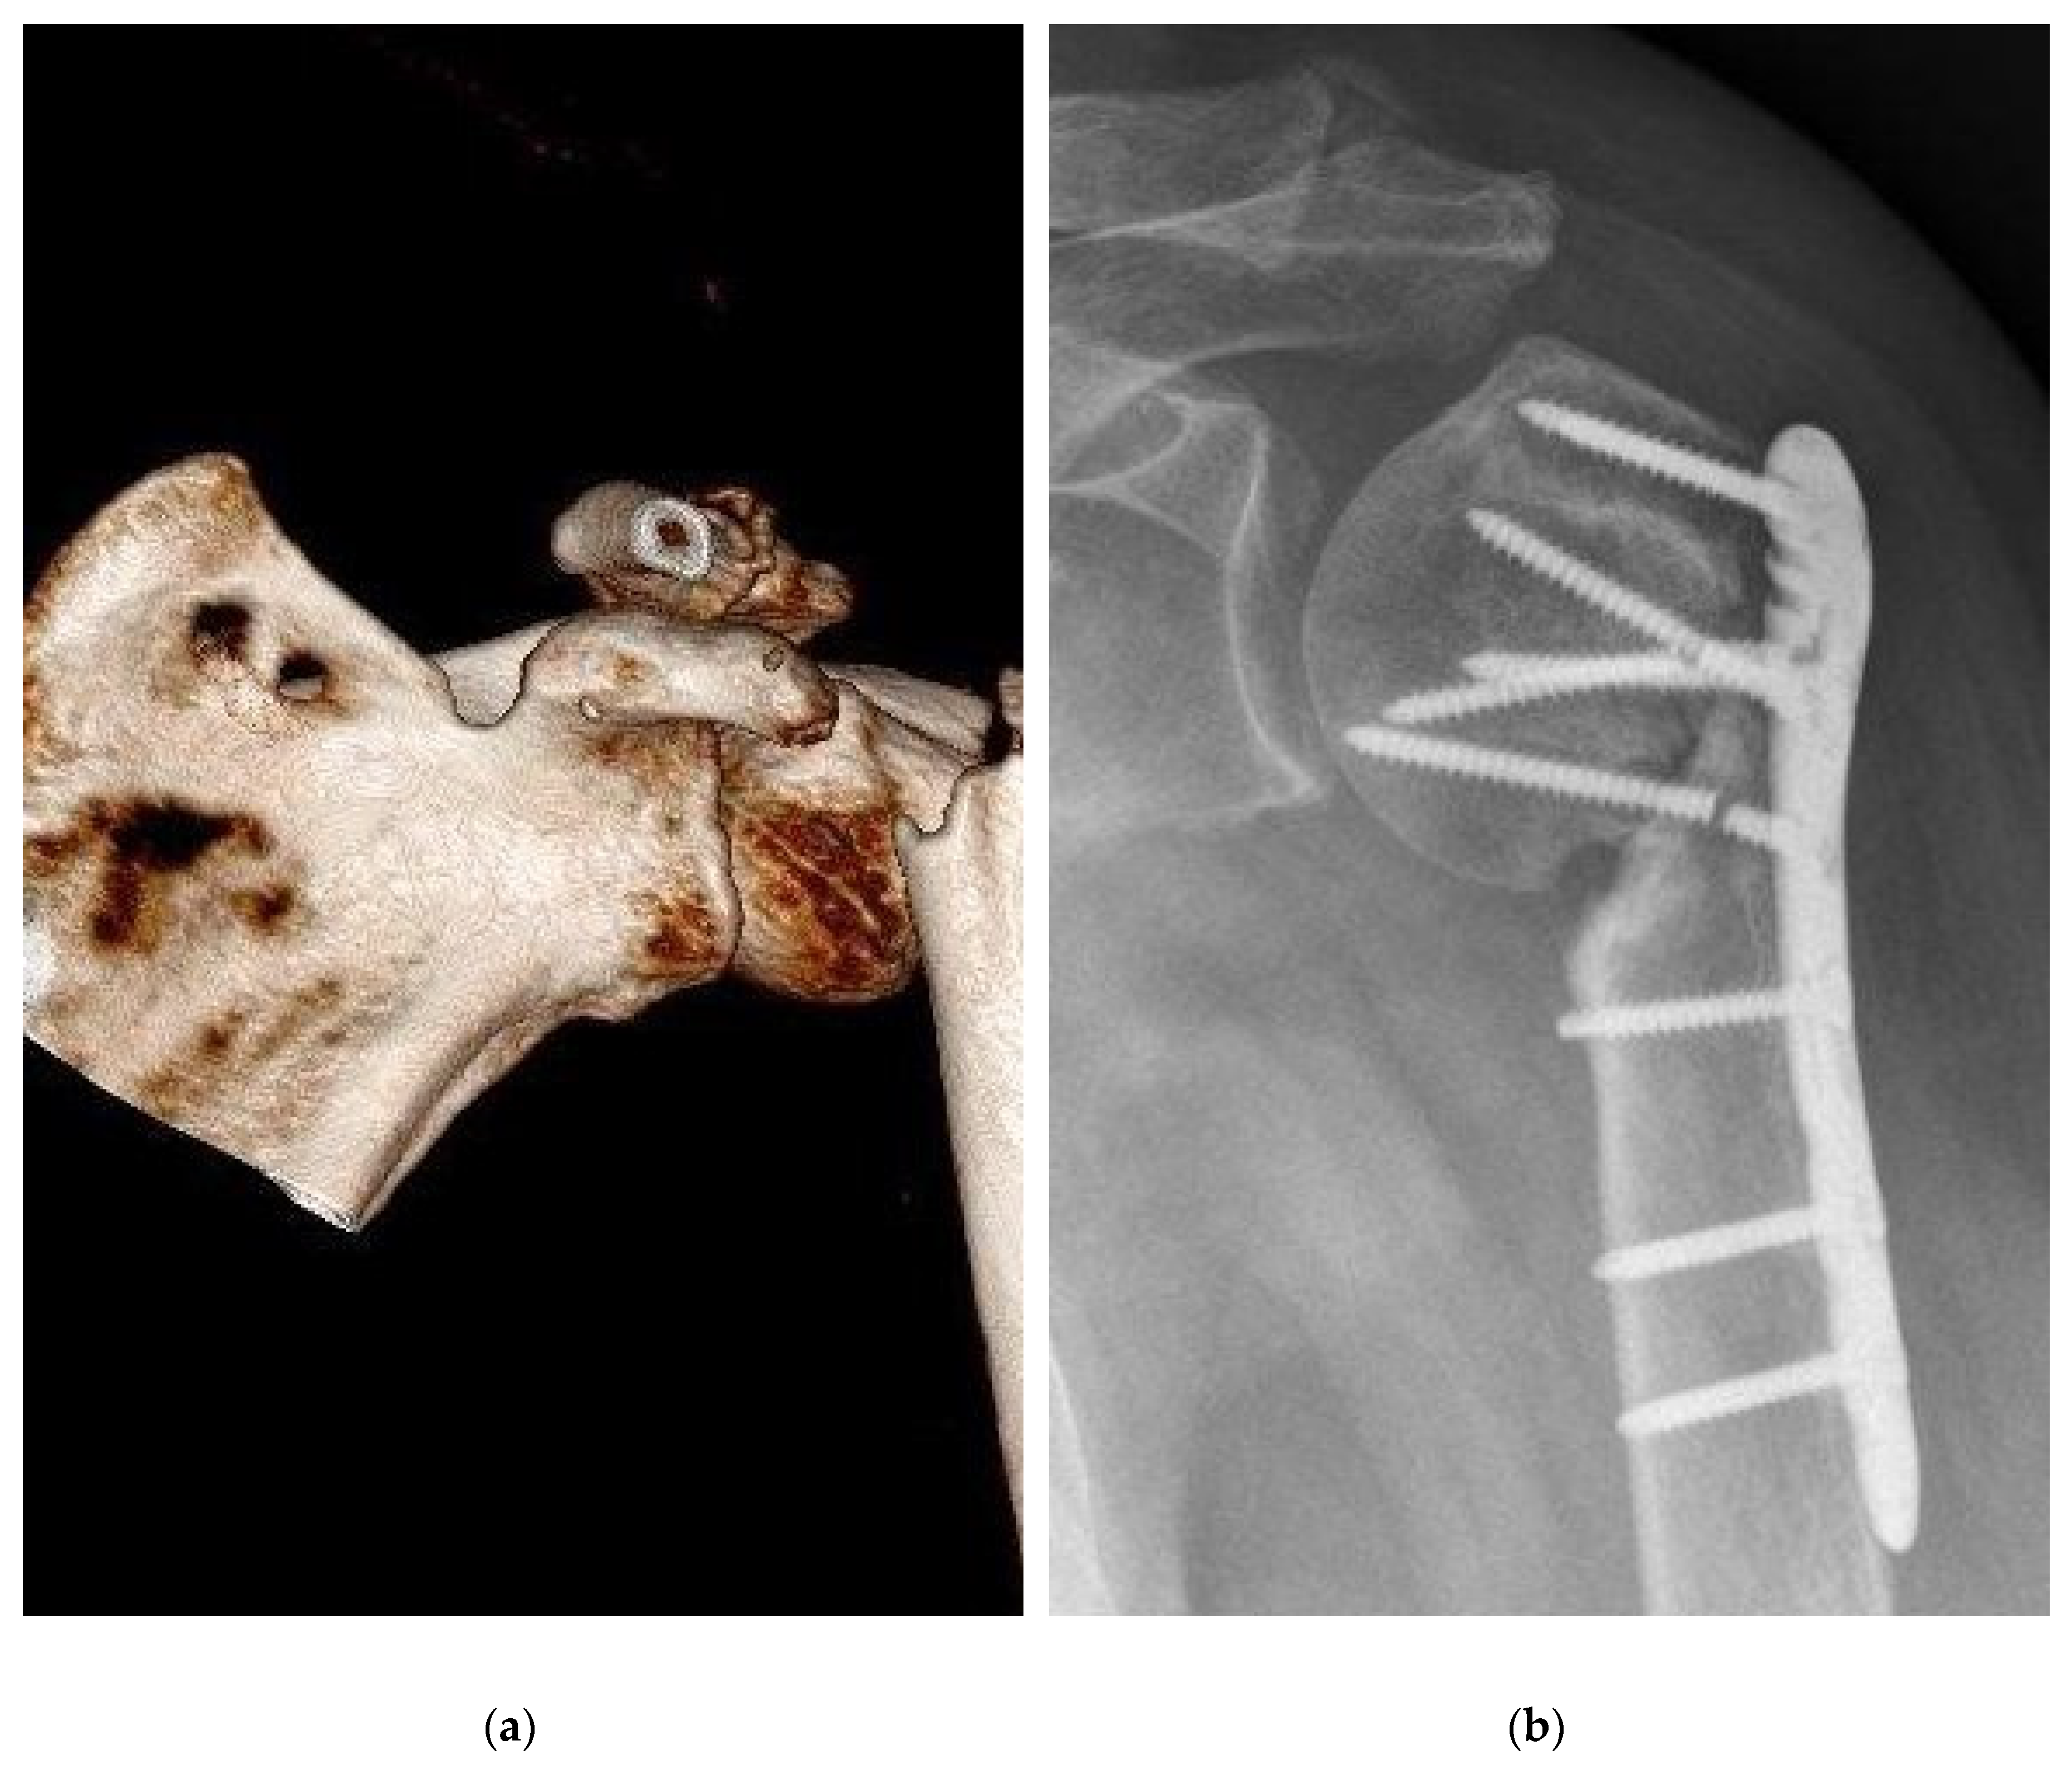

Figure 3. Severe complication, pseudarthrosis, resulting from a proximal humeral fracture resulted by empty defect treatment. (a) Preoperative 3D CT reconstruction showed a sub capital humeral fracture; (b) post-surgical care radiograph examination demonstrated an atrophic nonunion. Furthermore, two screws of the humeral head were broken.